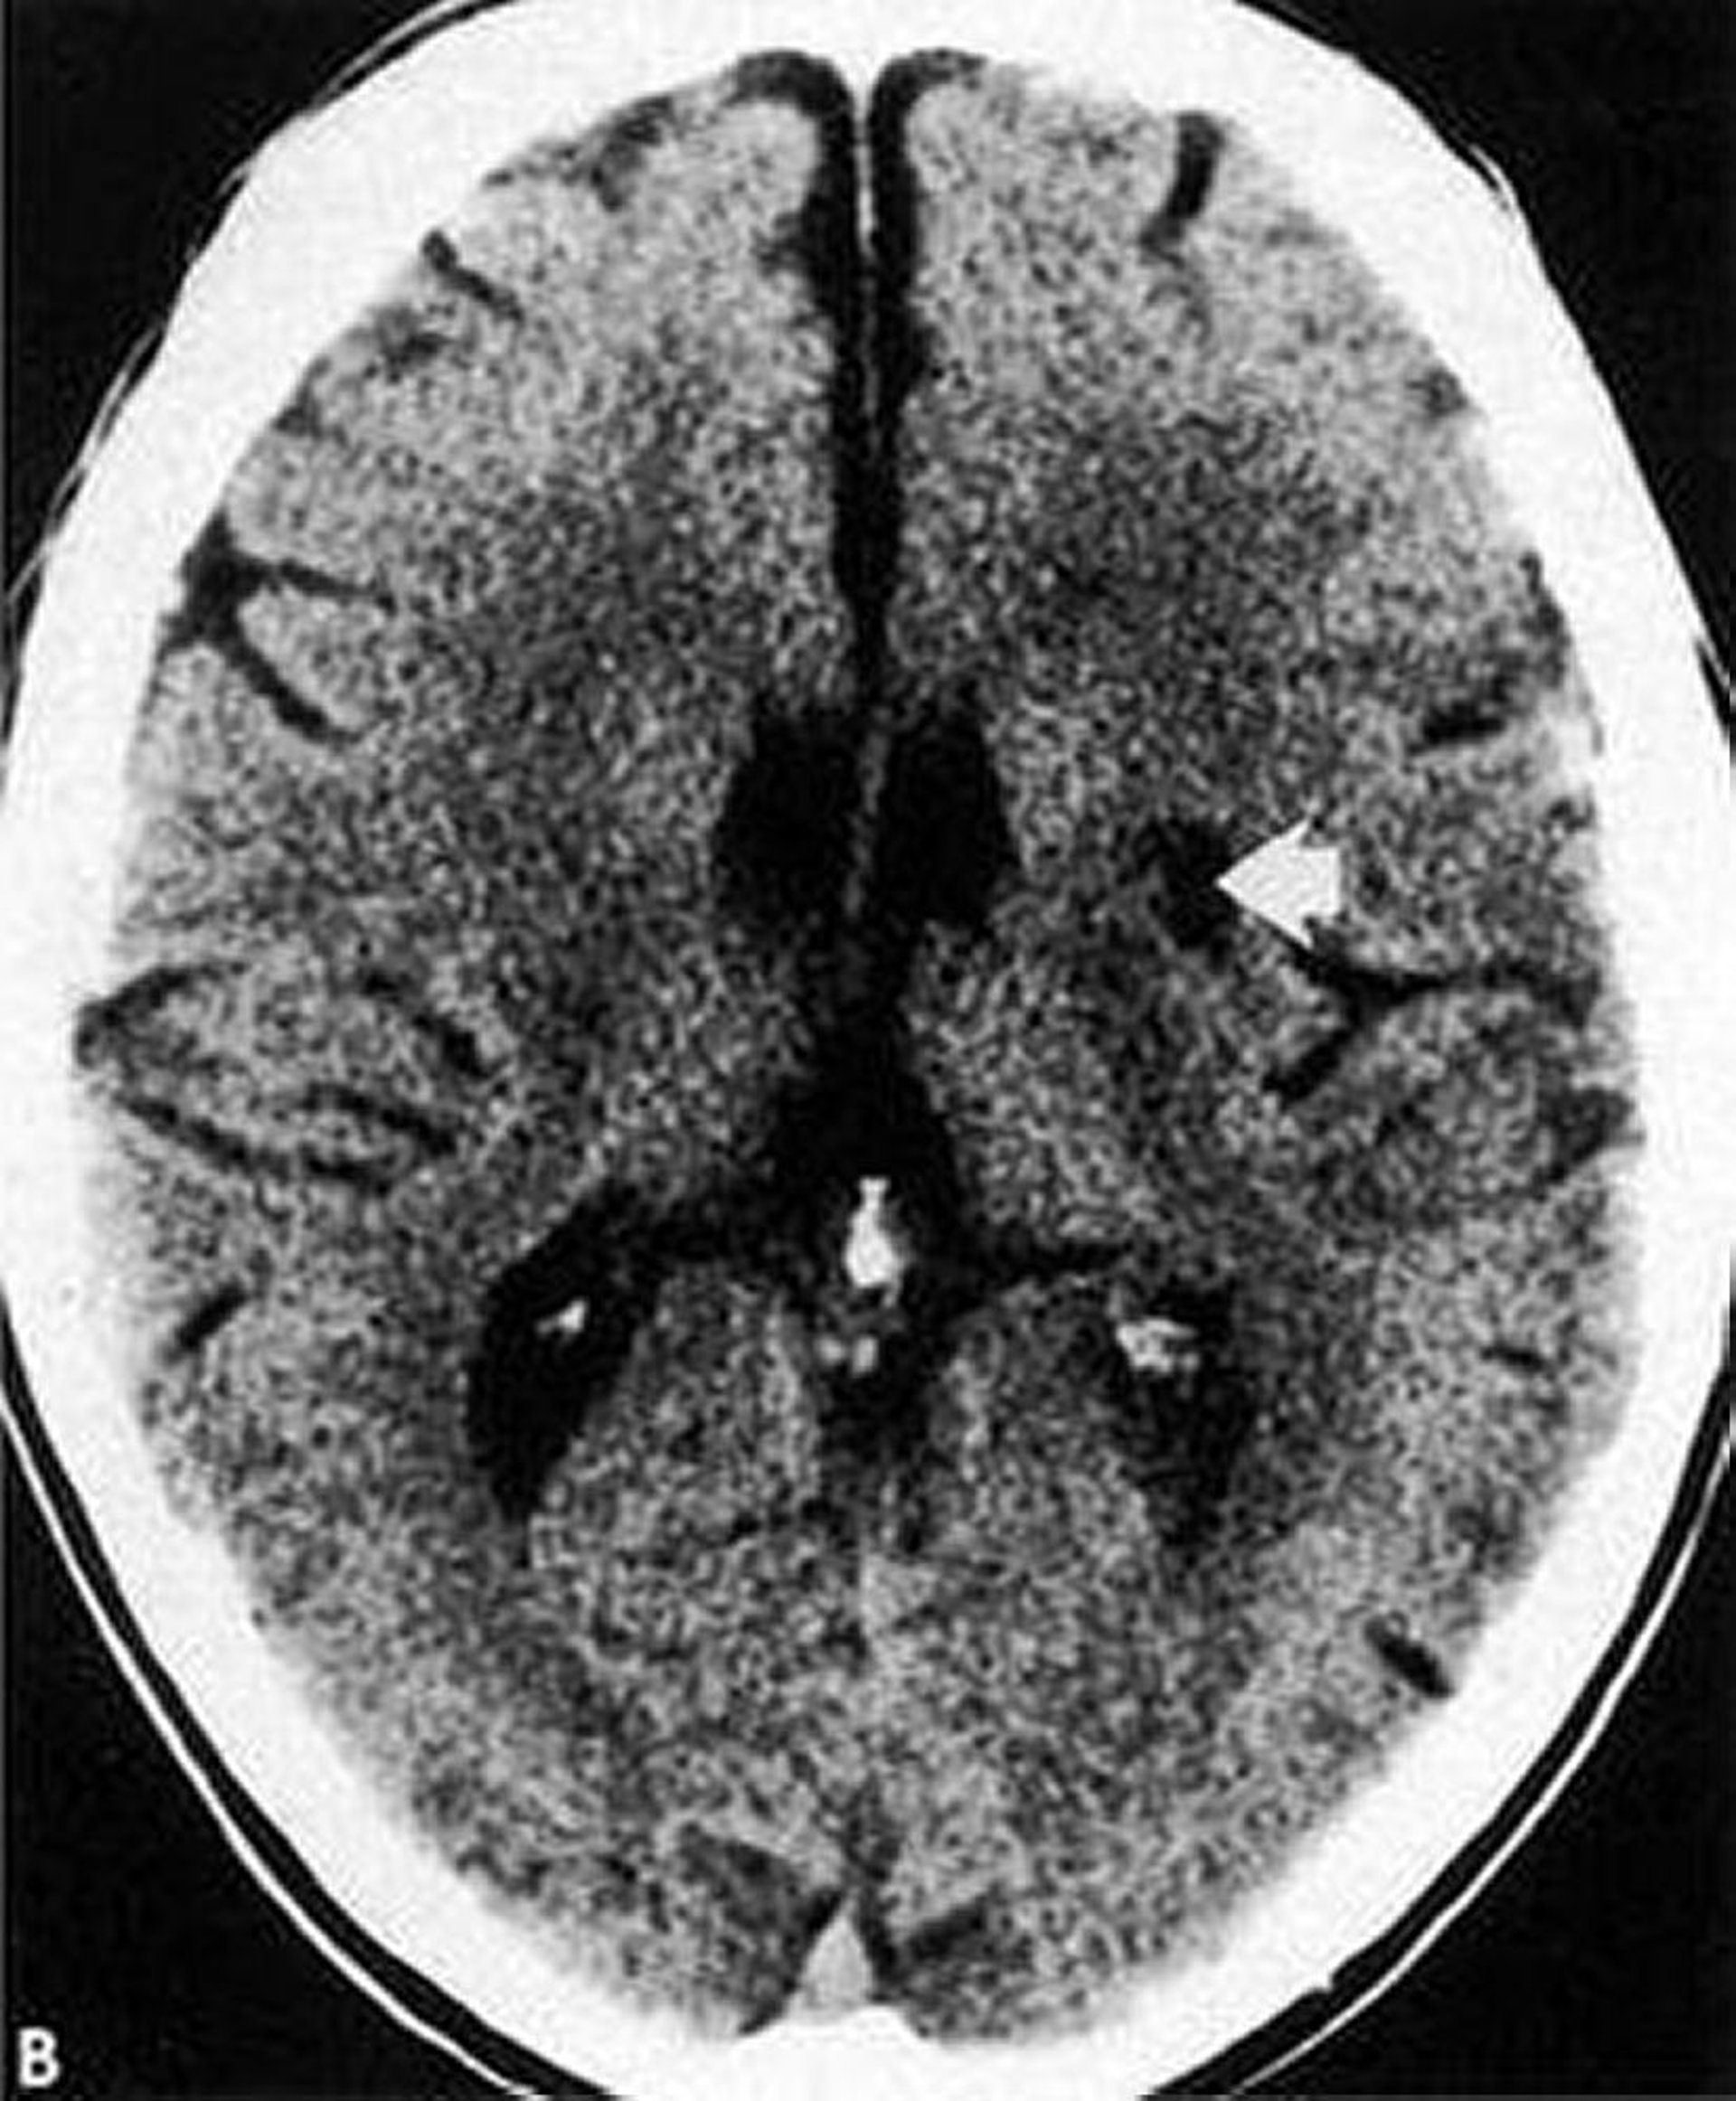

Esta TC muestra un infarto lacunar de baja densidad bien definido (flecha) dentro de los ganglios basales.

By permission of the publisher. From Geremia G, Greenlee W. In Atlas of Cerebrovascular Disease. Edited by PB Gorelick and MA Sloan. Philadelphia, Current Medicine, 1996.